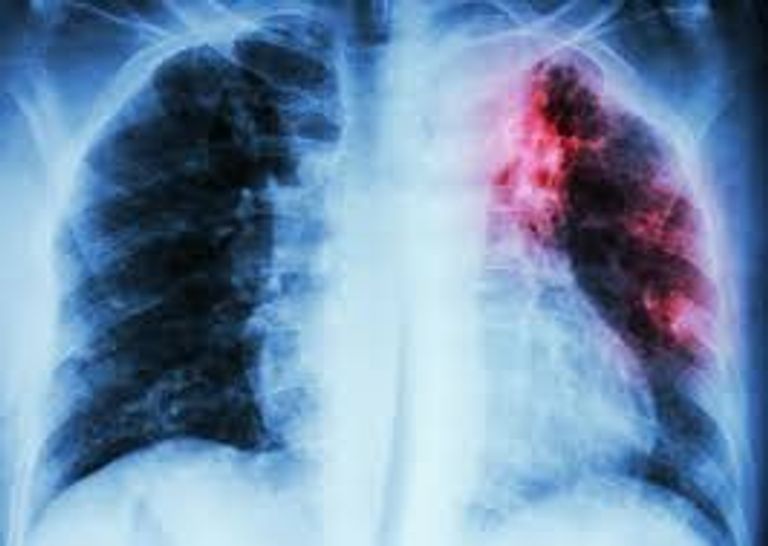

والسل، أحد أقدم وأخطر الأمراض المعدية في العالم، عادة ما يصيب الرئتين لكنه يمكن أن يؤثر على أجزاء أخرى من الجسم مثل العمود الفقري والدماغ والكلى. ورغم تطوير مضادات حيوية لعلاجه منذ الأربعينيات، ظهرت سلالات مقاومة جعلت العلاج أكثر صعوبة، بما في ذلك سلالات مقاومة متعددة للأدوية.